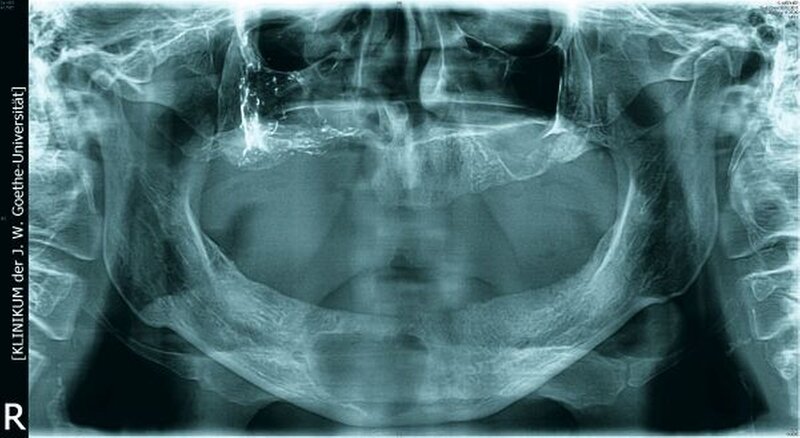

Bei der klinischen Inspektion imponierte ein desolates Gebiss bei starkem Knochenabbau und großflächigem Nekroseareal vestibulär im ersten Quadranten. Die Restbezahnung bestand aus den Zähnen 17, 15, 11 bis 24, 27 sowie 43 und 44. Alle Zähne wiesen Lockerungsgrad III auf. Neben einer spontanen Zahnfleischblutung konnte an mehreren Stellen eine putride Sekretion aus dem Parodontalspalt beobachtet werden. Des Weiteren wies der Patient einen enorm fauligen Foetor ex ore auf.

Die Computertomografie der Nasennebenhöhlen (NNH-CT) (nativ) zeigte dann das Ausmaß der knöchernen Destruktion. Neben der ausgedehnten generalisierten Nekrose des Oberkiefers konnte nebenbefundlich eine zystische Läsion im Bereich des Unterkiefers Regio 41 bis 45 diagnostiziert werden. Voraussichtlich ging diese vom Wurzelrest des Zahnes 41 aus. Weiterhin bestand eine totale Verschattung beider Sinus maxillaris und eine akzentuierte Lymphadenopathie in allen abgebildeten Leveln.